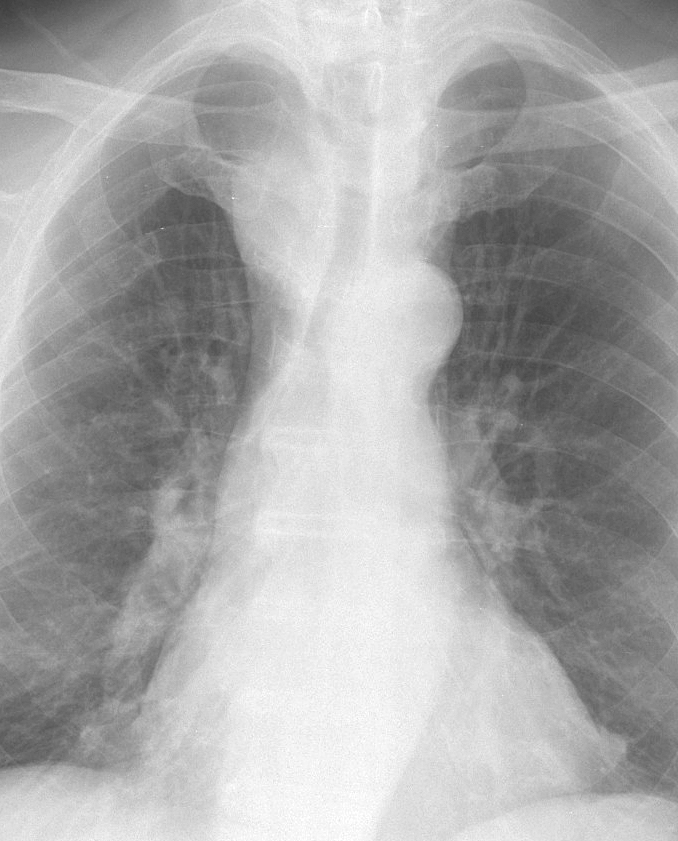

Mediastinum

Thyroid

Thyroid Mass Case 3 PA

Thyroid Mass

Case 3 PA